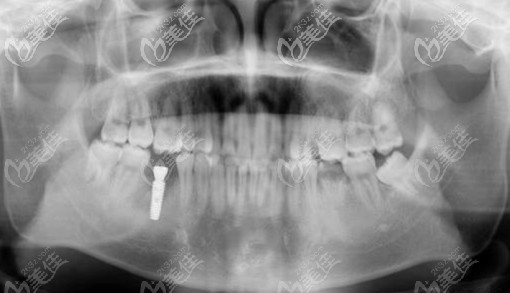

醫(yī)生介紹:劉明舟,是植得口腔河南的院長(zhǎng),也是Dentium種植系統(tǒng)國(guó)內(nèi)技術(shù)總監(jiān)及培訓(xùn)老師。出身于牙醫(yī)世家,畢業(yè)于口腔醫(yī)學(xué)專業(yè)。擅長(zhǎng)項(xiàng)目:?jiǎn)晤w種植牙、多顆種植牙、半口/全口種植牙、各類疑難種植病例、牙齒美學(xué)修復(fù)等項(xiàng)目。醫(yī)生簡(jiǎn)介:劉明舟院長(zhǎng),先后進(jìn)修學(xué)習(xí)于西安第四、、種植牙醫(yī)院、韓國(guó)Dentium、德國(guó)Ankylos等種植牙專業(yè)機(jī)構(gòu)...